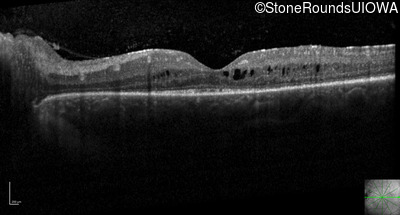

Optical Coherence Tomography - Right - 20/30 -2